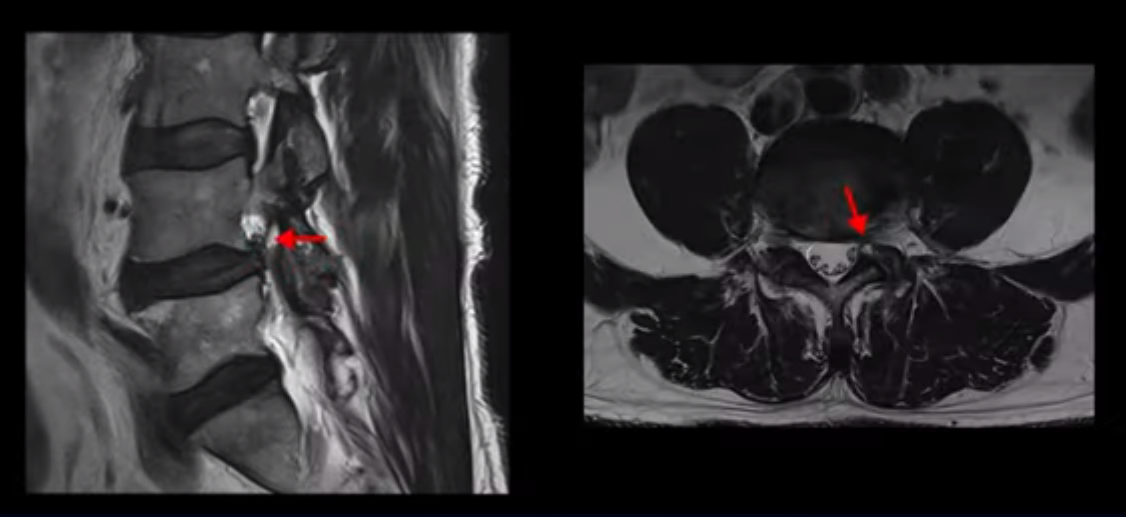

이분 허리 MRI를 보면 60세가 넘었기 때문에 퇴행이 진행은 되었지만 아주 심하지는 않습니다.

이분 왼쪽 다리가 저리고 아파서 2~3년 전부터 걷기가 힘들었는데 이분 허리 4번, 5번 마디에 신경 가지가 빠져나가는 추간공이 다른 마디에 비해서 좁아져 있습니다. 하지만 아주 심하게 좁아져 있지는 않습니다.

의사마다 MRI를 보고 얘기가 달랐다고 하는데 심하지 않다고 하는 쪽이 맞습니다. 그런데 이분은 신경 구멍 넓이에 비해 증상은 매우 심한 편입니다. 왜 그럴까요? 이 이유와 어떻게 치료하는지에 대해 지금부터 설명해 드립니다.